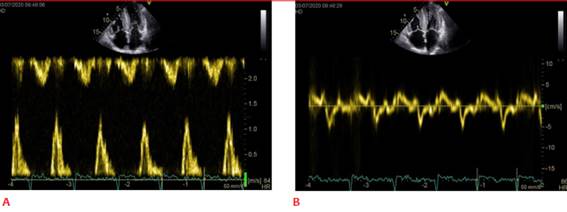

El compromiso de la función diastólica es una de las características principales de AC. En etapas precoces de la enfermedad es característico que presenten cavidad ventricular pequeña con FEVI preservada y disfunción diastólica marcada. Habitualmente el patrón de llenado restrictivo se observa en estadios avanzados de la enfermedad (figuras 2A y 2B).

Figura 2: A. Llenado de VI restrictivo. B. Doppler tisular con velocidades tisulares disminuidas, onda s′, a′ y e′ muestran velocidades tisulares < 5 cm/seg (signo de “5-5-5”).

Es típico de la AC la presencia de velocidades tisulares disminuidas tanto de la velocidad de desplazamiento sistólico como de las diastólicas. Un signo típico, pero tardío, es el “5-5-5” que implica que las velocidades tisulares de onda s′, e′ y a′ son menores a 5 cm/seg7 (figura 2B).